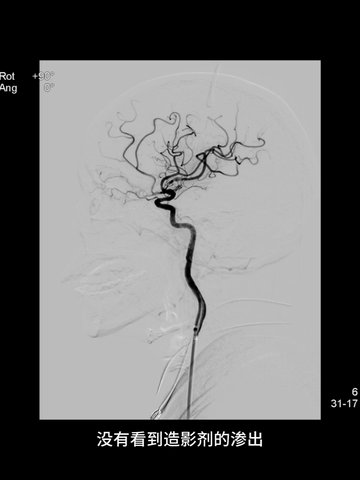

海绵窦段中间管回血通畅后,造影示右ICA和MCA完全再通,前向血流良好。

放大造影示:右MCA下干近端痉挛狭窄;等待5分钟后造影见痉挛改善。

后续造影见右MCA下干痉挛明显改善;但右ACA显影不佳。